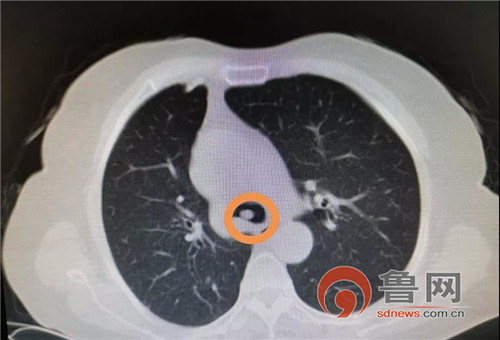

鲁网9月3日讯(记者 于建军 通讯员 褚雪松) 60岁的患者于女士3年前做了肺部肿瘤的开胸手术,3个月前突然出现胸闷、憋气。近日,在即墨区人民医院经过胸部CT检查,发现肺部肿瘤转移压迫到大气道,阻塞右侧主支气管导致呼吸困难,病人随时有可能窒息死亡,情况非常危急!

CT提示隆突新生物,镜下示隆突新生物几乎完全堵塞右主支气管管腔,部分阻塞左主支气管管腔。